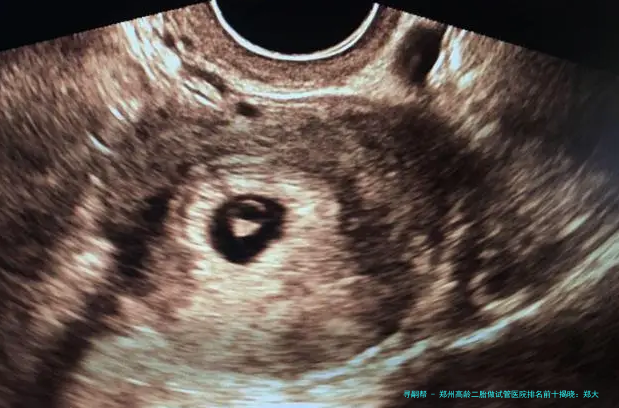

| 阴道B超监测卵泡(次) | 200 | 80 | 120 | 100-150 |